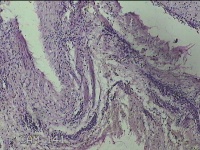

左侧外阴囊肿壁

性别

女

年龄

35岁

临床诊断

左外阴囊肿

一般病史

发现外阴囊肿2年余,加重3月。

标本名称

大体所见

灰白暗红色囊壁样组织5.5x2.8x0.7cm一堆,表面光滑,部分已切开,囊内容物已流失,囊壁厚0.1cm。

图3

具体位置,考虑巴氏腺囊肿。